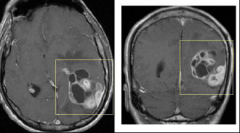

脑海绵状血管瘤的国外治疗

由于视力下降明显、视野缺损严重,40多岁张先生就医后被诊断为...